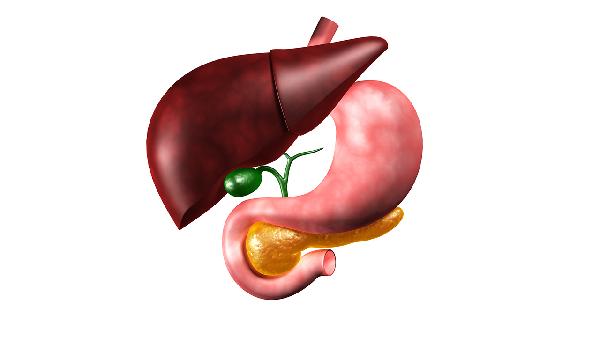

肝脏就像人体的“化工厂”,每天默默处理着各种毒素和代谢废物。可这个任劳任怨的器官有个特点——痛觉神经少,等它“喊疼”时往往已经晚了。秋天干燥的气候更容易加重肝脏负担,这些伤肝行为你可能天天在做!

肝癌高发?医生警告:这5件事不做,肝脏迟早出问题! 一、5个最伤肝的生活习惯1、熬夜追剧到凌晨 肝脏在晚上11点到凌晨3点工作效率最高,这个时段不睡觉,肝脏就无法完成毒素清理。长期熬夜会导致转氨酶升高,脂肪肝风险增加47%。 2、把饮料当水喝 含糖饮料会促使肝脏将多余糖分转化为脂肪。每天喝两罐可乐的人,患非酒精性脂肪肝的概率是普通人的2.5倍。秋季干燥更要多喝温水。 3、乱吃“护肝片” 某些保健品可能含有不明成分,反而加重肝脏代谢负担。临床发现,乱吃保健品导致的药物性肝损伤占比高达23%。 4、生闷气不发泄 中医说“怒伤肝”是有道理的。情绪压抑时,体内儿茶酚胺分泌增加,直接损害肝细胞。建议通过运动、倾诉等方式及时疏导情绪。 5、爱吃腌制食品 咸菜、腊肉等含亚硝酸盐的食物,需要肝脏加倍工作来解毒。秋季新鲜果蔬丰富,建议多选择当季的梨、葡萄等护肝水果。

肝癌高发?医生警告:这5件事不做,肝脏迟早出问题! 二、肝脏发出的求.救信号1、皮肤变黄:胆红素代谢异常 2、蜘蛛痣:雌激素灭活能力下降 3、异常疲劳:能量合成障碍 4、牙龈出血:凝血因子合成减少 三、秋季养肝的3个黄金法则1、饮食“三多三少” 多优质蛋白(鱼、豆制品)、多深色蔬菜、多喝水;少油腻、少酒精、少加工食品。特别推荐秋季应季的枸杞菊花茶。 2、作息“早睡早起” 顺应秋季“早卧早起”的养生原则,保证23点前入睡。中午11-13点可以小憩20分钟,有助于肝血回流。 3、运动“适度有氧” 选择快走、游泳等温和运动,每周3-5次,每次30分钟左右。避免剧烈运动造成乳酸堆积。

肝癌高发?医生警告:这5件事不做,肝脏迟早出问题! 肝脏的健康管理重在预防和日常养护。从现在开始调整生活习惯,给这个沉默的器官多一点关爱。记住,最好的“护肝药”就藏在你的生活方式里。 温馨提示:内容中医疗科普知识仅供参考,不构成用药指南,不作诊断依据,无行医资格切勿自行操作,若有不适请及时到医院就诊。 (责任编辑:admin) |